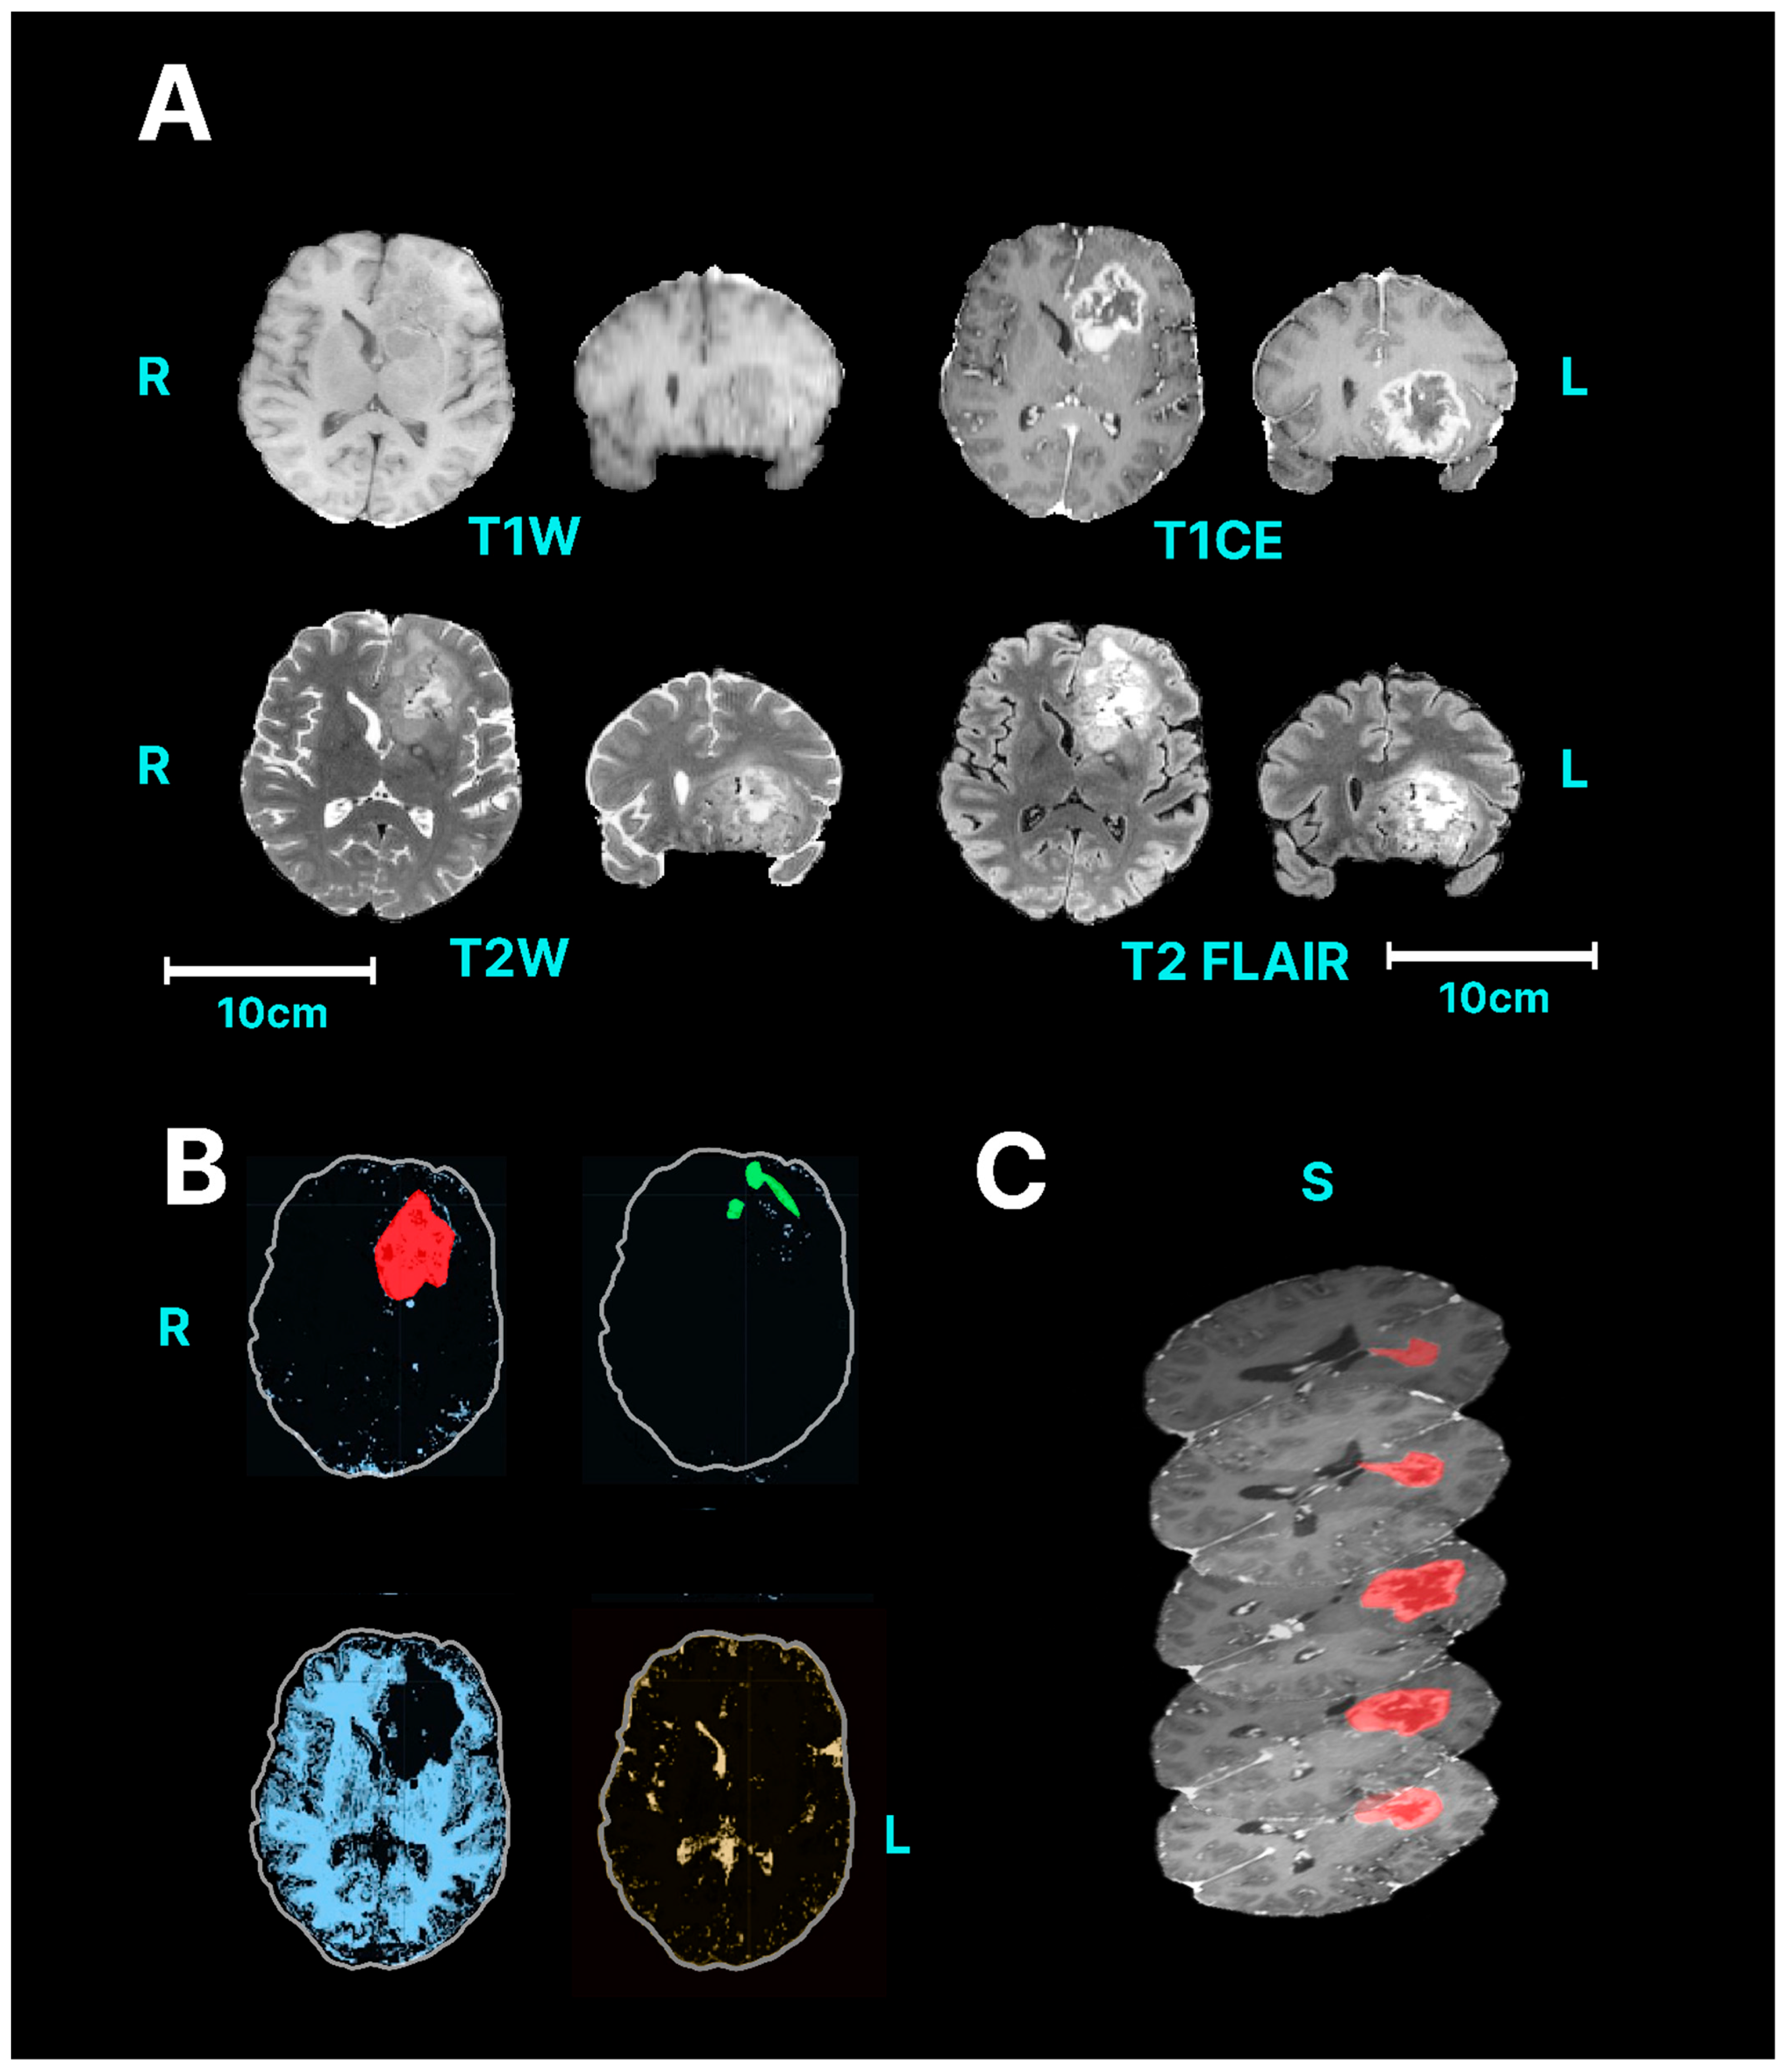

| Glioblastoma (GBM) | T1w T1w + contrast T2w T2 FLAIR/TIRM | GBMs are generally hyperintense on T2-weighted images but are hypo- or isointense on T1-weighted images [38]. GBM often have enhancing and non-enhancing components. Necrosis is typically visible as a low signal intensity (SI) on T1-enhanced MRI and located at the centre of the lesion [39]. Cystic components of a GBM are typically T2W hyperintense and T1 hypointense, with a well-defined thin wall. There can also an area of oedema surrounding the tumour that is visible in T2 FLAIR scans [38]. |